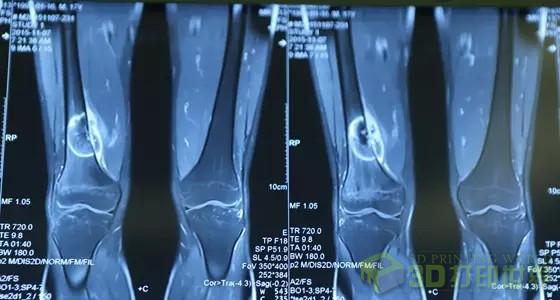

17岁的小张被诊断出右腿患有股骨远端骨肉瘤。骨肉瘤在原发性恶性骨肿瘤中发病率位居首位,并且恶性程度很高,截肢后3至5年存活率仅为5%至20%,对患者的生活质量乃至生命危害甚大。为了保险起见,一般的股骨远端骨肉瘤保肢手术需要将患者瘤侧骨段,包括临近关节全部切除,置换成人工关节。但是在关节囊、韧带等重要组织被拿掉后,关节功能将受到影响,患者可能出现行动上的不便。同时,由于人工关节的使用寿命只有5至10年,患者将来还需要进行多次手术替换关节,而反复手术可能导致患者骨量越来越少,最终依旧面临着截肢的困境。

考虑到患者才17岁,还有很长的人生道路要依靠健康、完整的双腿去践行。在中南大学“湘雅名医”、湘雅医院骨科主任胡懿郃教授的支持下,何洪波教授术前仔细分析患者病情及接受术前新辅助化疗后的效果,决定在术中采用3D打印技术辅助手术,为小张彻底切除肿瘤的同时,保留正常关节。